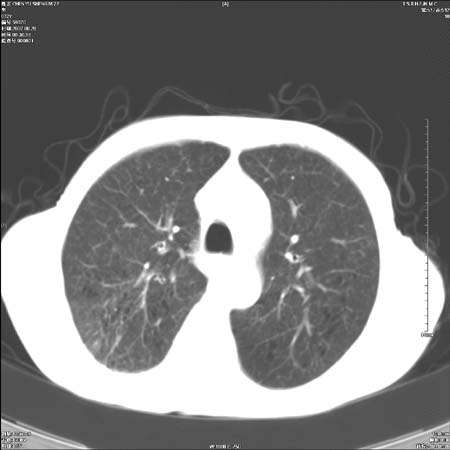

男性,72岁,既往肺结核,今复查。无前片对比。

右侧中央型肺癌伴中叶不张可能性大,建议增强扫描.右上肺陈旧性肺结核.慢性支气管炎伴肺气肿.右侧少量胸腔积液.

右侧中央型肺癌伴中叶不张可能性大,建议纤支镜检查.右上肺陈旧性肺结核.肺气肿。

典型右肺中心型肺癌

右侧中央型肺癌伴肺不张可能性大,建议增强扫描.右上肺陈旧性肺结核.慢性支气管炎伴肺气肿.右侧少量胸腔积液.

右肺中心型肺癌

右侧中央型肺癌.上肺陈旧性肺结核.

1右侧中央型肺癌伴中叶不张2右侧少量胸腔积液3右上肺陈旧性肺结核

1.右肺中心性肺癌并右肺中叶综合征2。右侧胸腔少量积液3。右肺上叶结核球已钙化,4。慢支伴肺气肿

右侧中央型肺癌伴中叶不张可能性大,建议纤支镜检查.右上肺陈旧性肺结核.肺气肿。

右侧中央型肺癌伴中叶不张可能性大,建议增强扫描.右上肺陈旧性肺结核.慢性支气管炎伴肺气肿.右侧少量胸腔积液.

右侧中央型肺癌伴中叶不张

右肺中央型肺癌伴右肺中叶不张。

右上肺陈旧性肺结核。

支持右肺中心型肺癌并中叶不张,右上肺陈旧性肺结核钙化,右侧少量胸腔积液。

支持右侧中央型肺癌伴中叶不张可能性大,建议增强扫描.右上肺陈旧性肺结核.慢性支气管炎伴肺气肿.右侧少量胸腔积液.

支持 1右侧中心型肺癌伴中叶不张2右侧少量胸腔积液3右上肺陈旧性肺结核4双肺局限性肺气肿

1,右侧中央型肺癌.

2,右上肺陈旧性肺结核.

1.右侧中央型肺癌伴中叶不张,建议纤支镜检查.

2.右上肺陈旧性肺结核.

3.肺气肿。

4.右侧少量胸腔积液.

右侧中央型肺癌伴中叶不张并纵隔淋巴结增大,建议增强扫描.右上肺陈旧性肺结核.慢性支气管炎伴肺气肿.右侧少量胸腔积液。

右肺中心型肺癌并肺不张,陈旧性肺tb.慢支,肺气肿.

陈旧性肺结核.慢性支气管炎伴肺气肿,中央型肺癌伴中叶不张。

右侧中央型肺癌伴中叶不张可能性大;右上肺陈旧性肺结核.慢性支气管炎伴肺气肿

陈旧性结核是存在,但真正致命的却是右侧中心型肺癌。